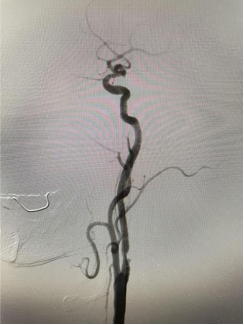

(右側(cè)頸內(nèi)動脈治療前) (左側(cè)頸內(nèi)動脈治療前)

患者是一位古稀老人,已飽受高血壓病困擾,1月前行頭頸血管檢查可見雙側(cè)頸內(nèi)動脈狹窄80%以上,其發(fā)生中風(fēng)風(fēng)險極高?;颊呒覍僬业缴窠?jīng)內(nèi)科尋求進一步診治。因為患者高齡,雙側(cè)頸動脈嚴重狹窄,無頸動脈內(nèi)膜剝脫術(shù)(CEA)指征,科室團隊討論后決定為其行頸動脈支架植入術(shù)(CAS)。對于介入治療,該患者也面臨同期或分期完成雙側(cè)頸動脈支架植入治療的選擇。分期雙側(cè)頸動脈支架植入有增加病人痛苦、住院時間長和費用增加的缺點,以及術(shù)中、術(shù)后低灌注引起未治療側(cè)腦梗死,術(shù)后高灌注造成治療側(cè)腦出血等風(fēng)險。同期雙側(cè)頸動脈支架植入術(shù)增加手術(shù)操作的時間和難度,雙側(cè)頸動脈狹窄同時解除會使顱內(nèi)血流迅速增加,與分期手術(shù)相比,可能會增加潛在的高灌注綜合征發(fā)生的風(fēng)險,同時刺激雙側(cè)頸動脈竇壓力感受器,可能會導(dǎo)致更嚴重、持久的血流動力抑制,甚至心跳驟停。通過與家屬積極溝通,科室團隊充分討論后,決定采用同期雙側(cè)頸內(nèi)動脈支架植入術(shù)治療方案??剖覉F隊完善術(shù)前準備,制定各項手術(shù)應(yīng)急預(yù)案和措施,手術(shù)順利。術(shù)后科室團隊密切監(jiān)護患者生命體征,無神經(jīng)功能缺損癥狀出現(xiàn),現(xiàn)患者痊愈出院。